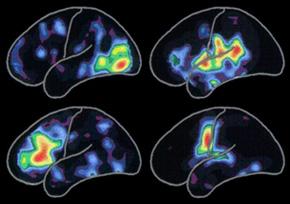

大腦皮層(Cortex):「思想縐紋」